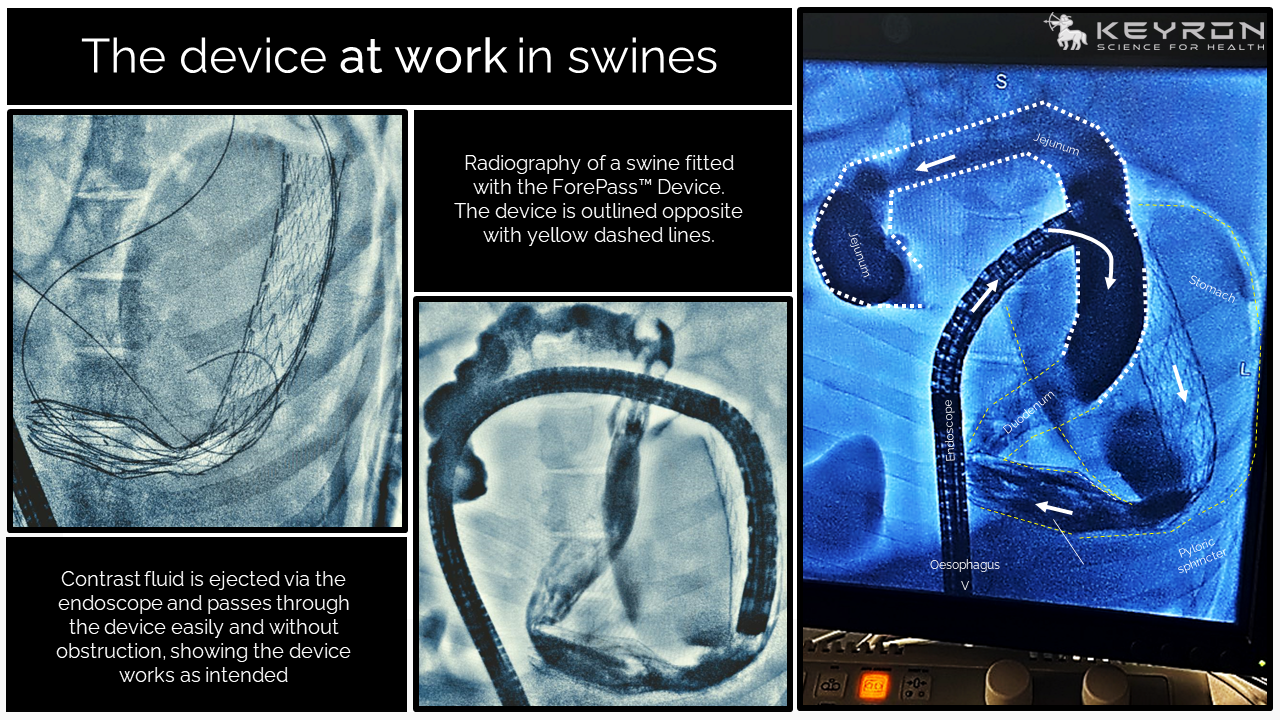

Long-Term Safety & Efficacy in Swine

Our large animal data was published in Gut, the world’s leading journal in gastroenterology and hepatology, and the official journal of the British Society of Gastroenterology, with an exceptionally high impact factor of 25.8.

Pre-clinical studies have shown that the efficacy of ForePass ® may be unprecedented, and likely even better than Roux-en-Y Gastric Bypass surgery. Our long-term animal data shows (Δ from Baseline vs endoscopic controls):

- -79% Weight Gain

- -37% Total Blood Sugar (AUC)

- -45% Blood Sugar Over Time

- +59% Insulin Sensitivity

- -61% Liver Sugar Production

Proven Long-Term Safety

Proven Correct and Stable Long-Term Positioning